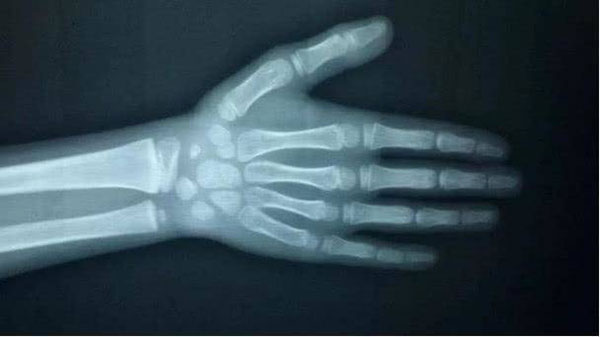

Sau khi nghe lời kể của người mẹ, bác sĩ cho rằng đây không phải là một hiện tượng tốt nên yêu cầu chụp X-quang bàn tay của bé. Kết quả cho thấy tuổi xương của Tingting đã tương đương với trẻ 11 tuổi, hơn 3 tuổi so với tuổi thực của cô bé. Điều đó cho thấy Tingting có dấu hiệu dậy thì sớm trước tuổi. Mặc dù cô bé chỉ cao hơn vài cm so với chiều cao trung bình của trẻ 8 tuổi (1,28m) nhưng lại thấp hơn 12cm so với chiều cao trung bình của trẻ 11 tuổi. Theo dự đoán của bác sĩ, trong tương lai khả năng chiều cao của bé chỉ dưới 1,5m.